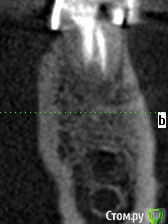

meld Опубликовано 7 ноября, 2017 Автор Поделиться Опубликовано 7 ноября, 2017 Прицельный снимок 38 зуба и его срезы Ссылка на комментарий

IvanK Опубликовано 7 ноября, 2017 Поделиться Опубликовано 7 ноября, 2017 ЗдравствуйтеЕсть периапикальные измененияя за удаление и последующую имплантацию 1 Ссылка на комментарий